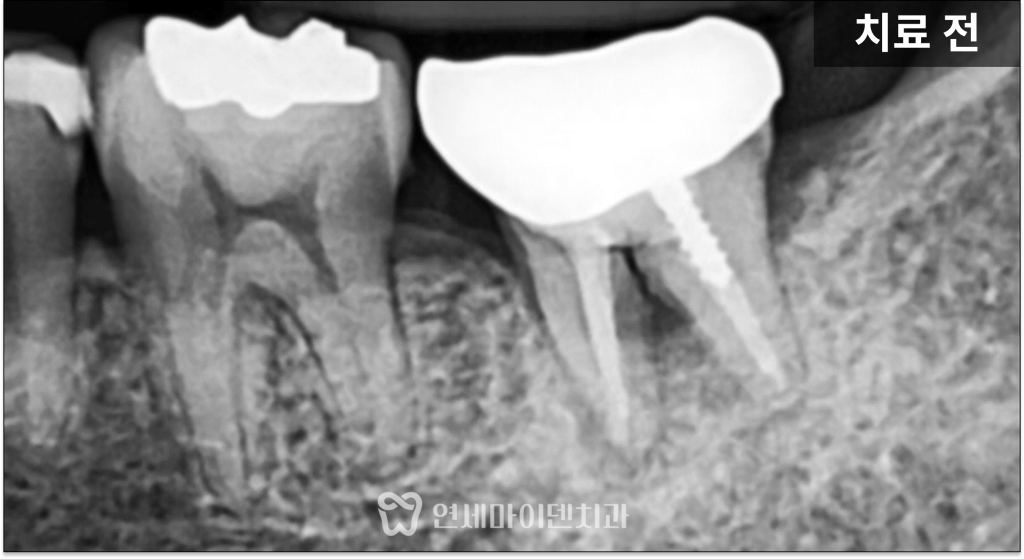

하지만 이 케이스에서는

치아 뿌리가 갈라지는 부위인

분지부까지 뼈가 녹아 있는 상태였습니다.

분지부 뼈가 손상되었다는 것은

치아를 지지하는 구조 자체가

무너졌다는 의미입니다.

분지부 뼈가 녹는 원인

치아 뿌리 사이의 분지부 뼈가 녹는 경우는

예후가 좋지 않은 경우가 많습니다.

이번 케이스에서는

과거 신경치료 과정 중

치아 내부에 불필요한 구멍이 생겼고,

이를 적절한 재료가 아닌

레진으로 덮어 마무리하면서

문제가 시작된 것으로 보였습니다.

레진은 이러한 부위에서

완전한 밀폐를 유지하기 어려워

시간이 지나면서 미세한 틈이 생기고,

그 틈을 통해 세균이 유입되면서

결국 분지부 뼈까지 녹게 되는 결과로

이어진 것입니다.